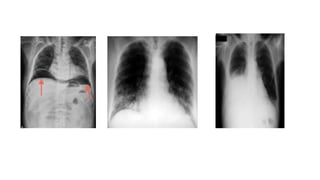

- Exámenes de imagen son

los estudios Rx de tórax,

abdomen Ultrasonografía

Neumonía

Neumonia